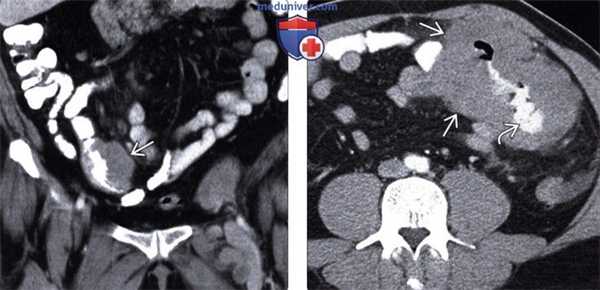

(Слева) На КТ с контрастным усилением в корональной плоскости у пациента с лимфомой визуализируется выраженное увеличение селезенки, а также множественные мелкие гиподенсные очаги В в ее паренхиме, в связи с диффузным лимфоматозным поражением селезенки.

(Справа) При аксиальной КТ с контрастным усилением определяется большое объемное образование, расположенное в селезенке, распространяющееся кнутри и прорастающее в желудок, который выглядит утолщенным по большой кривизне. Данные изменения являются проявлениями неходжкинской лимфомы (НХЛ). (Слева) При аксиальной КТ с контрастным усилением определяется диффузное увеличение и инфильтрация поджелудочной железы, внешне напоминающие панкреатит.

(Справа) При аксиальной КТ (с контрастом) у этого же пациента определяется распространенная лимфаденопатия брыжейки под поджелудочной железой. Обратите внимание на то, как лимфатический узел располагается вокруг брыжеечных сосудов; такое расположение часто описывается как «симптом сэндвича». Данные изменения, включая увеличение поджелудочной железы, являются проявлениями НХЛ.